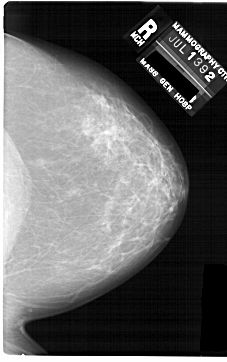

ics_version 1.0 filename A-1742-1 DATE_OF_STUDY 13 7 1992 PATIENT_AGE 48 FILM FILM_TYPE REGULAR DENSITY 3 DATE_DIGITIZED 3 3 1999 DIGITIZER HOWTEK 43.5 SEQUENCE LEFT_CC LINES 6871 PIXELS_PER_LINE 4096 BITS_PER_PIXEL 12 RESOLUTION 43.5 OVERLAY LEFT_MLO LINES 6871 PIXELS_PER_LINE 4666 BITS_PER_PIXEL 12 RESOLUTION 43.5 OVERLAY RIGHT_CC LINES 6871 PIXELS_PER_LINE 4306 BITS_PER_PIXEL 12 RESOLUTION 43.5 NON_OVERLAY RIGHT_MLO LINES 6871 PIXELS_PER_LINE 4606 BITS_PER_PIXEL 12 RESOLUTION 43.5 NON_OVERLAY |